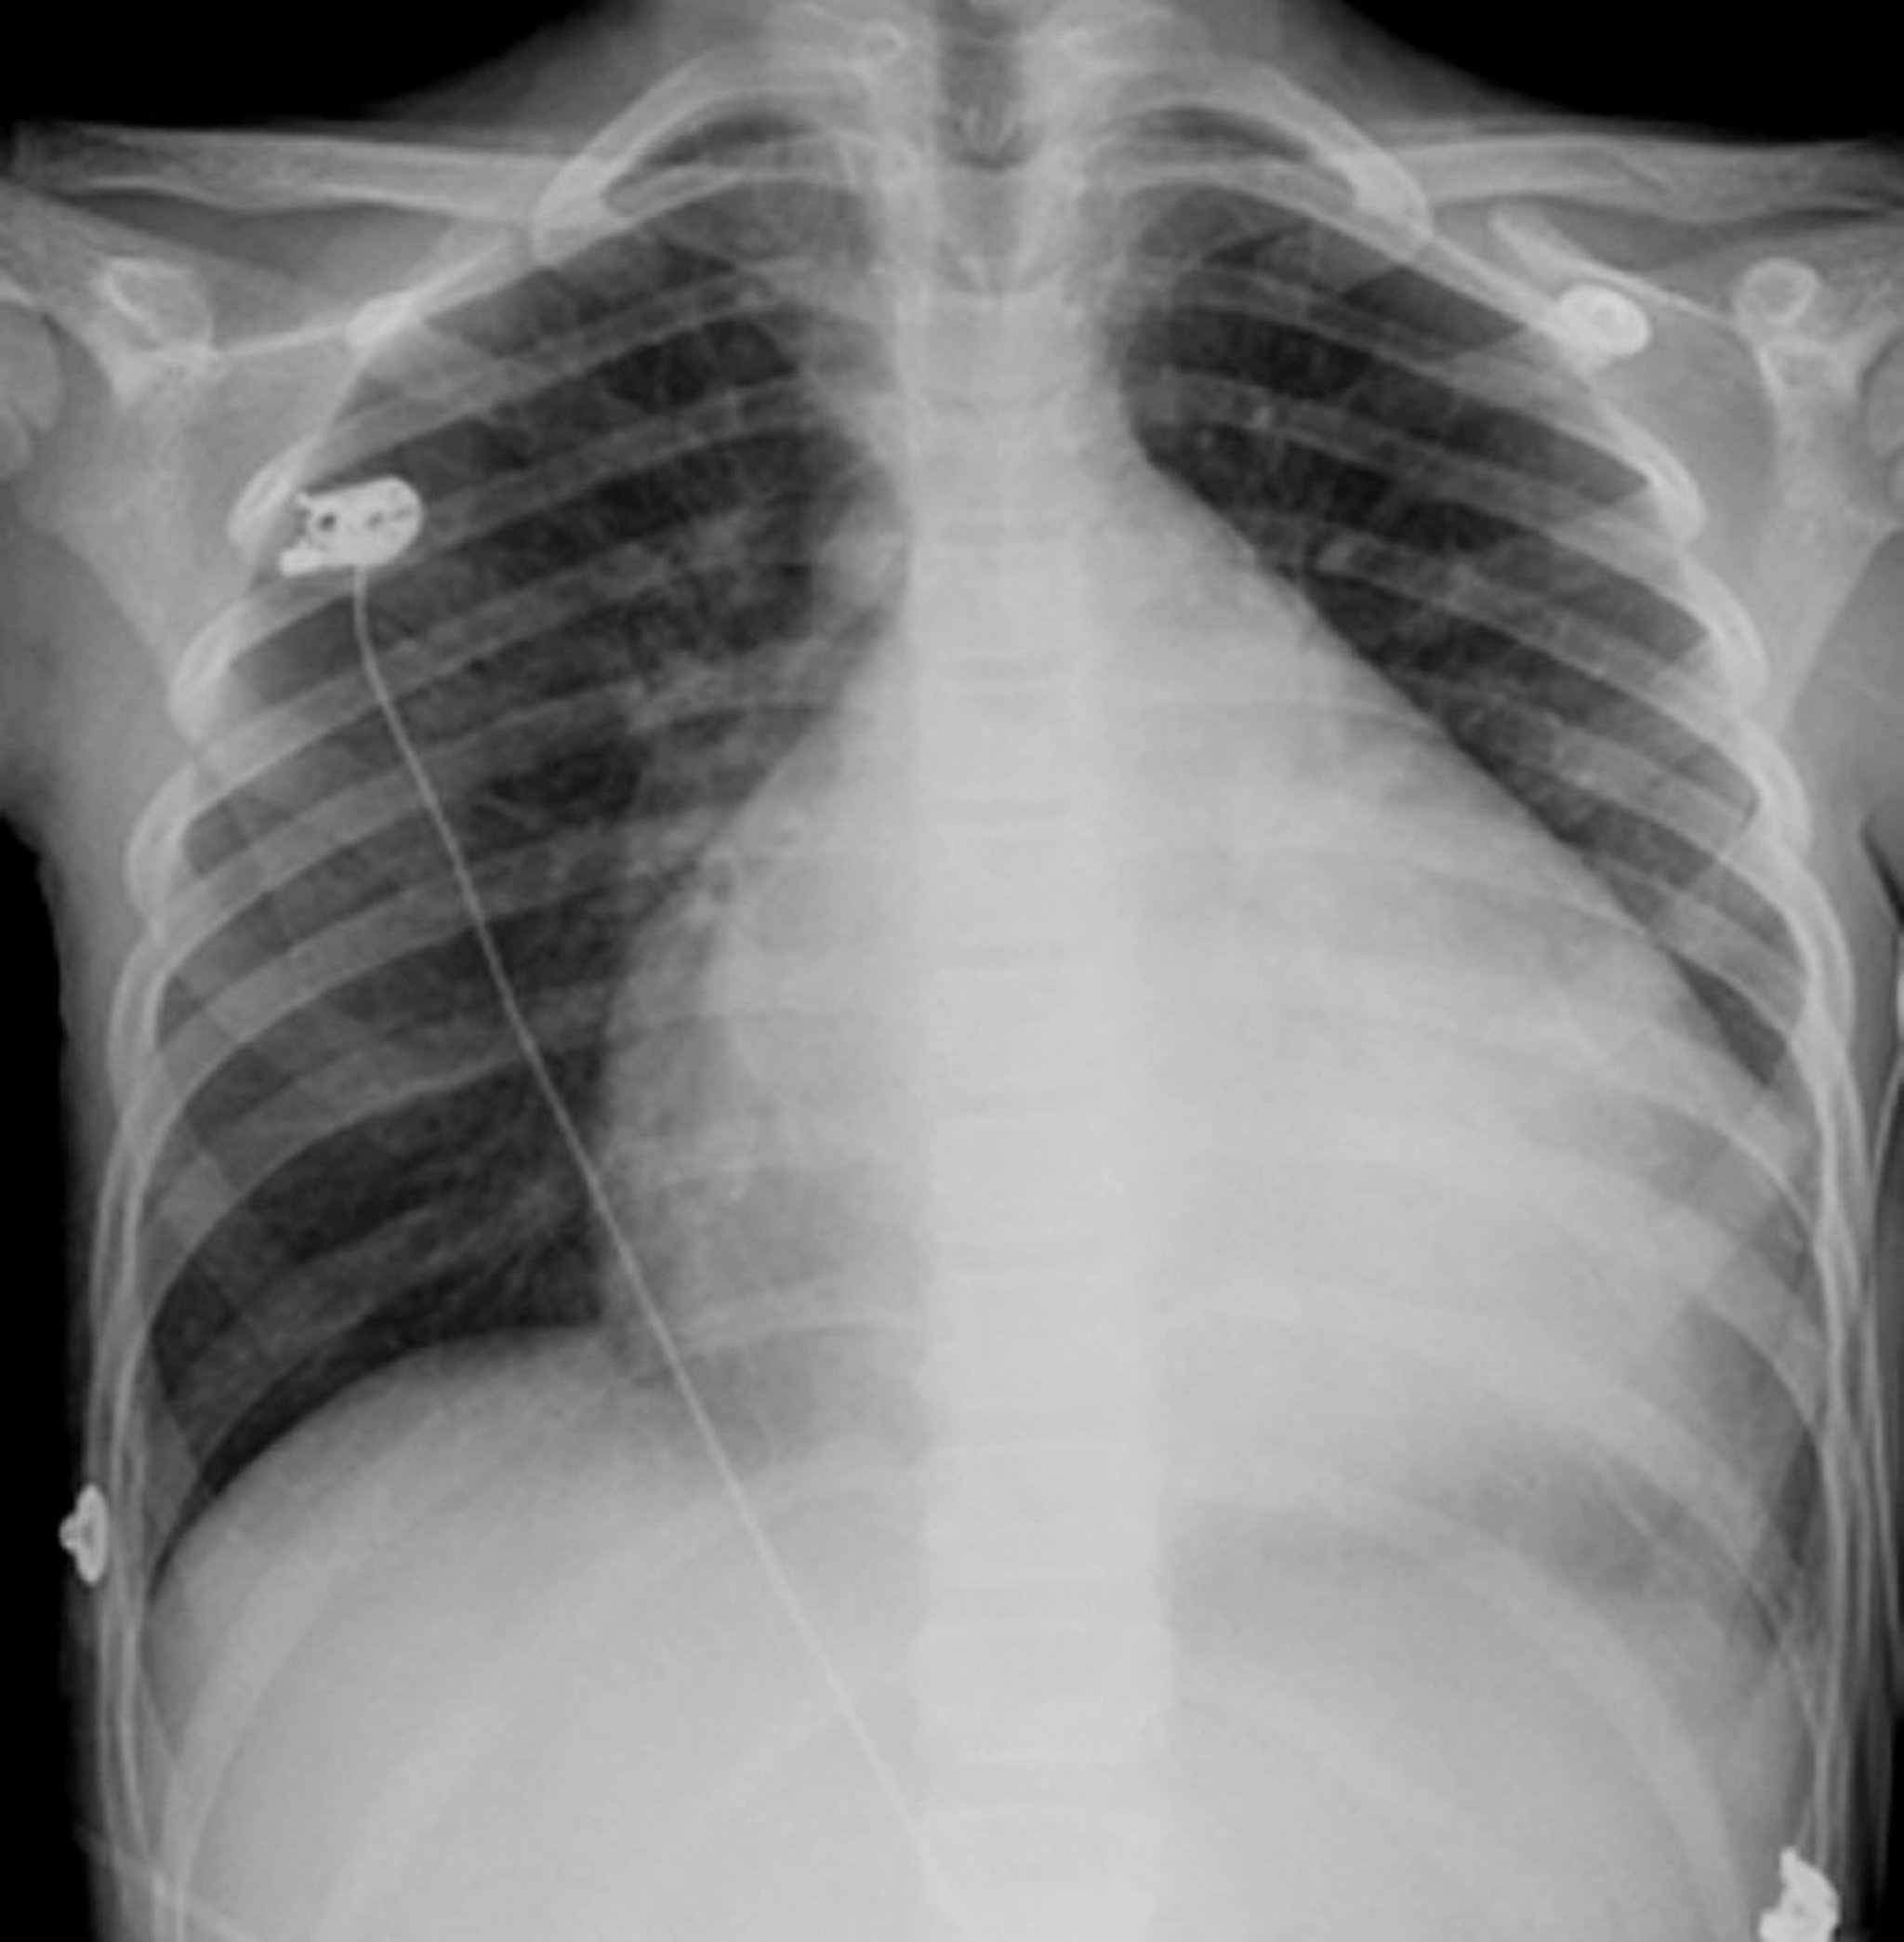

Vergrößertes Herz

Das Herz ist das kugelförmige weiße Objekt in der Mitte des Brustraums. Normalerweise nimmt es weniger als die Hälfte des Brustraums ein, doch bei dieser Person mit Kardiomyopathie nimmt das vergrößerte Herz fast drei Viertel des Brustraums ein.